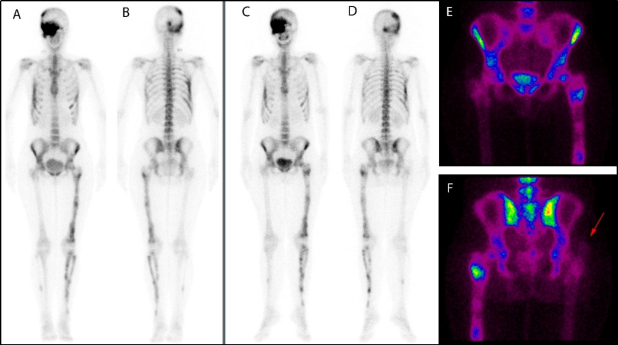

Paciente mujer de 37 años diagnosticada previamente de displasia fibrosa mediante gammagrafía ósea con 99mTc-HMDP realizada en 2015, que mostró un aumento de la captación hemicraneal derecha (involucrando regiones parietal, temporal, occipital y huesos del macizo facial), arcos costales (5º, 6º, 7º, 10º derechos y 6º izquierdo), miembro inferior izquierdo (fémur, tibia y peroné) y peroné derecho. Las lesiones eran sugestivas de displasia fibrosa poliostótica que fue posteriormente verificada mediante biopsia ósea realizada en la zona distal del fémur izquierdo y en el décimo arco costal posterior derecho (fig. 1, A y B). Durante la realización de una nueva gammagrafía ósea de seguimiento en 2021, la paciente refirió masa palpable en región glútea derecha de varios meses de evolución. La gammagrafía no mostró cambios significativos en la captación ósea relacionada con su displasia fibrosa ya conocida (fig. 1 C y D); sin embargo, se observó captación patológica en partes blandas de la región glútea derecha. Dada la clínica dolorosa en esa localización, se recomendó realizar una técnica de imagen morfológica para valorar mejor este hallazgo (fig. 1 E y F).